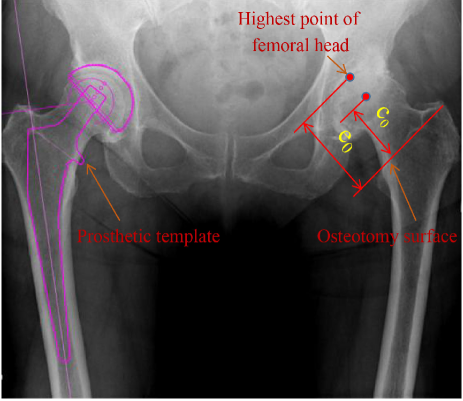

As shown in Figure 14, the patient’s right acetabulum was normal, but with defected in the left acetabulum development. According to the principle of symmetry, the position of the left osteotomy surface could be planned with reference to the right side before operation. If we measured the vertical distance e from the highest point of the femoral head to the osteotomy surface, we could then obtain the desired value c0subscript𝑐0c_{0} of the preoperative femoral neck length from the formula c0=e0rsubscript𝑐0subscript𝑒0𝑟c_{0}=e_{0}-r, where r was the rotation radius of the femoral head. Finally, according to the length of the femoral neck, the inner diameter of the femoral medullary cavity and the insertable depth of the femoral medullary cavity, the model of the prosthesis abled to be fit into the medullary cavity could be obtained from the manual. Figure 14 showed the template of the acetabular prosthesis implanted on the left side.

Refer to caption

Figure 14: Preoperative planning of desired femoral neck length.

1) As shown in Figure 7a, a 3D printed model (composed of a femur stalk inserted into a femur) was used to simulate anatomy measurement during surgery. The actual length c𝑐c of the rotation centre of the femoral head to the femoral surface was obtained using the end of an optical probe, which measured the distance from the highest point to the osteotomy surface, subtracted the radius of the femoral head prosthesis (Figure 7b). The coordinates P1subscript𝑃1P_{1} (x1subscript𝑥1x_{1}, y1subscript𝑦1y_{1}, z1subscript𝑧1z_{1}), P2subscript𝑃2P_{2} (x2subscript𝑥2x_{2}, y2subscript𝑦2y_{2}, z2subscript𝑧2z_{2}), and P3subscript𝑃3P_{3} (x3subscript𝑥3x_{3}, y3subscript𝑦3y_{3}, z3subscript𝑧3z_{3}) of the three reference points were obtained sequentially from the osteotomy surface of the affected limb, and the coefficients A𝐴A, B𝐵B, C𝐶C, and D𝐷D of the osteologic surface equation were calculated using equation (1).

The measurement point of the femoral spheroid prosthesis was the highest point, P4subscript𝑃4P_{4} (x4subscript𝑥4x_{4}, y4subscript𝑦4y_{4}, z4subscript𝑧4z_{4}), on the femoral spherical prosthesis. The formula (2) was used to calculate the distance between the osteotomy surface of the affected limb and the measurement point e𝑒e.

where x𝑥x, y𝑦y, and z𝑧z represented the coordinate values of the measurement points; and e𝑒e represented the distance between the osteotomy surface of the affected limb and the measurement point.

The measurement results of the surgical robot for the hip morphological parameters of the patient were as follows: When the robot reached the desired coordinate point, if no feedback adjustment was added, the average errors of the forward tilt angle and abduction angle (Figure 11a, Figure 11c) were 0.99° and 1.79°, respectively. After feedback was added to adjust the attitude of the robot, the average errors of the forward tilt angle and abduction angle (Figure 11b, Figure 11d) were 0.22° and 0.15°, respectively. After the robot arm reached the desired value, the output data of the optical positioner was fed back to improve the accuracy of the grinding angle. According to CAD models of the femoral neck prostheses, the sizes of the red, blue, and white femoral heads were 58, 59, and 60 mm, respectively. As shown in Figure 12, the average error of the distance from the highest point of femoral bulb prosthesis to the osteotomy surface, as measured using optical probes, were 0.071, 0.118, and 0.087 mm, respectively. For comparison, the average errors measured using the mechanical equipment were 0.287, 0.278, and 0.307 mm. Thus, it was demonstrated that the optical probe had much higher precision and could effectively assist surgeons in performing THA surgery.